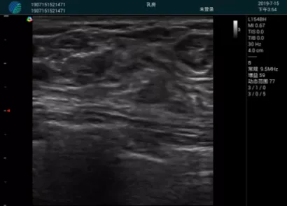

便攜超聲引導(dǎo)下人流術(shù)

病例一:

清晰顯示孕囊,通過軟件包計(jì)算孕齡7w+6d

M20實(shí)時(shí)引導(dǎo),術(shù)中清晰顯示孕囊被破壞和抽吸針的過程,清晰顯示吸引針

抽吸結(jié)束后縱切子宮,孕囊已被完全抽吸,未見明顯殘留

橫切子宮,發(fā)現(xiàn)右側(cè)宮腔靠近宮角處有少許脫模樣殘留

M20引導(dǎo)下,抽吸針找到右側(cè)宮角處再次清掃

二次抽吸后再次進(jìn)行超聲檢查,宮腔未見殘留,宮腔線清晰顯示

超聲引導(dǎo)下可視化人流是技術(shù)安全性的保障,一般對人流術(shù)設(shè)備預(yù)算不高,M20具備婦產(chǎn)科軟件包,且穿透力圖像質(zhì)量好,既滿足人流引導(dǎo)需要,也可用于床旁超聲的需求。